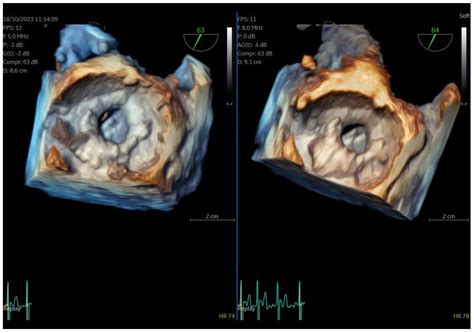

Cardiovascular health is a critical aspect of overall well-being, and early detection of heart issues can significantly improve outcomes. One of the essential diagnostic tools in this realm is the Tee Cardiac Test, also known as Transesophageal Echocardiography (TEE). This non-invasive procedure provides detailed images of the heart's structure and function, making it invaluable for diagnosing various cardiac conditions.

The Tee Cardiac Test involves inserting a flexible tube with a transducer at its tip into the esophagus. This transducer emits ultrasound waves that create detailed images of the heart. Unlike traditional echocardiography, which is performed externally, TEE offers a closer view of the heart, particularly the back structures that are harder to visualize from the chest.